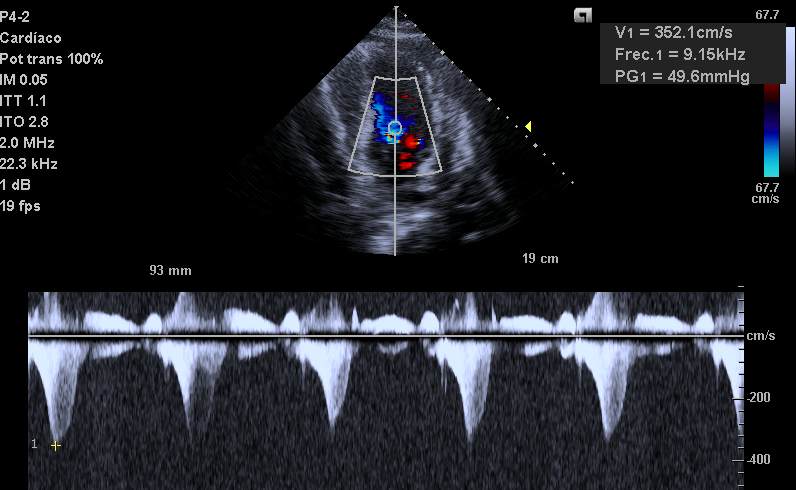

Also..LV looks very empty. LV walls can get too close together and obstruct the flow of blood!

Obstruction causes blood to speed up! (think of thumb on a hose).

Velocity is 3.5 m/s (very fast) with a gradient of 50 mmHg! This is Hemodynamically significant obstruction!

Fluid did help: BP now 105/69, gradient improved from 50 to 24 mmHg!

Gradient is now 4.8 mmHg (Not hemodynamically significant!)